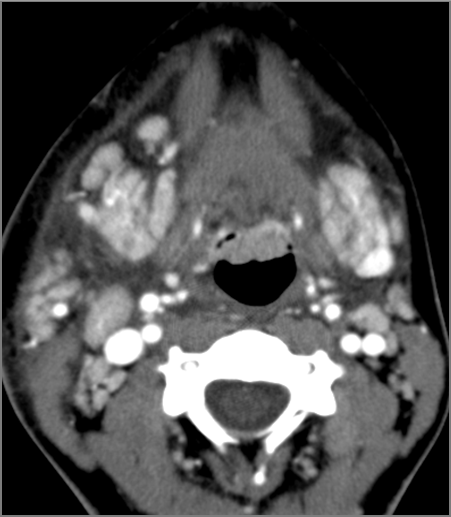

Hypopharynx, Larynx, Deep Neck and Entire Retropharyngeal Space

There is edema/abscess within the adjacent deep neck, and/or retropharyngeal space. [Yes/No]